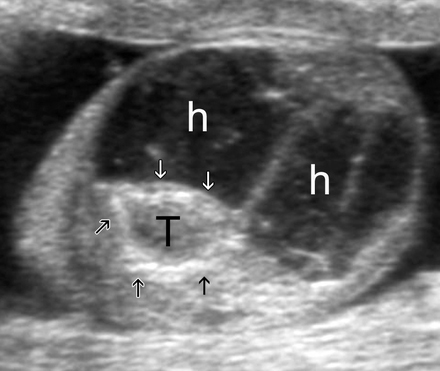

[Figure caption and citation for the preceding image starts]: Longitudinal ultrasound scan in a newborn with discoloration of the right testicle at birth showing the testis (T) surrounded by a highly echogenic tunica (arrows), which is probably calcified; a complex hydrocele (h) with several septa occupies the scrotal sacAso C, et al. RadioGraphics. 2005;25:1197-1214. Used with permission [Citation ends].